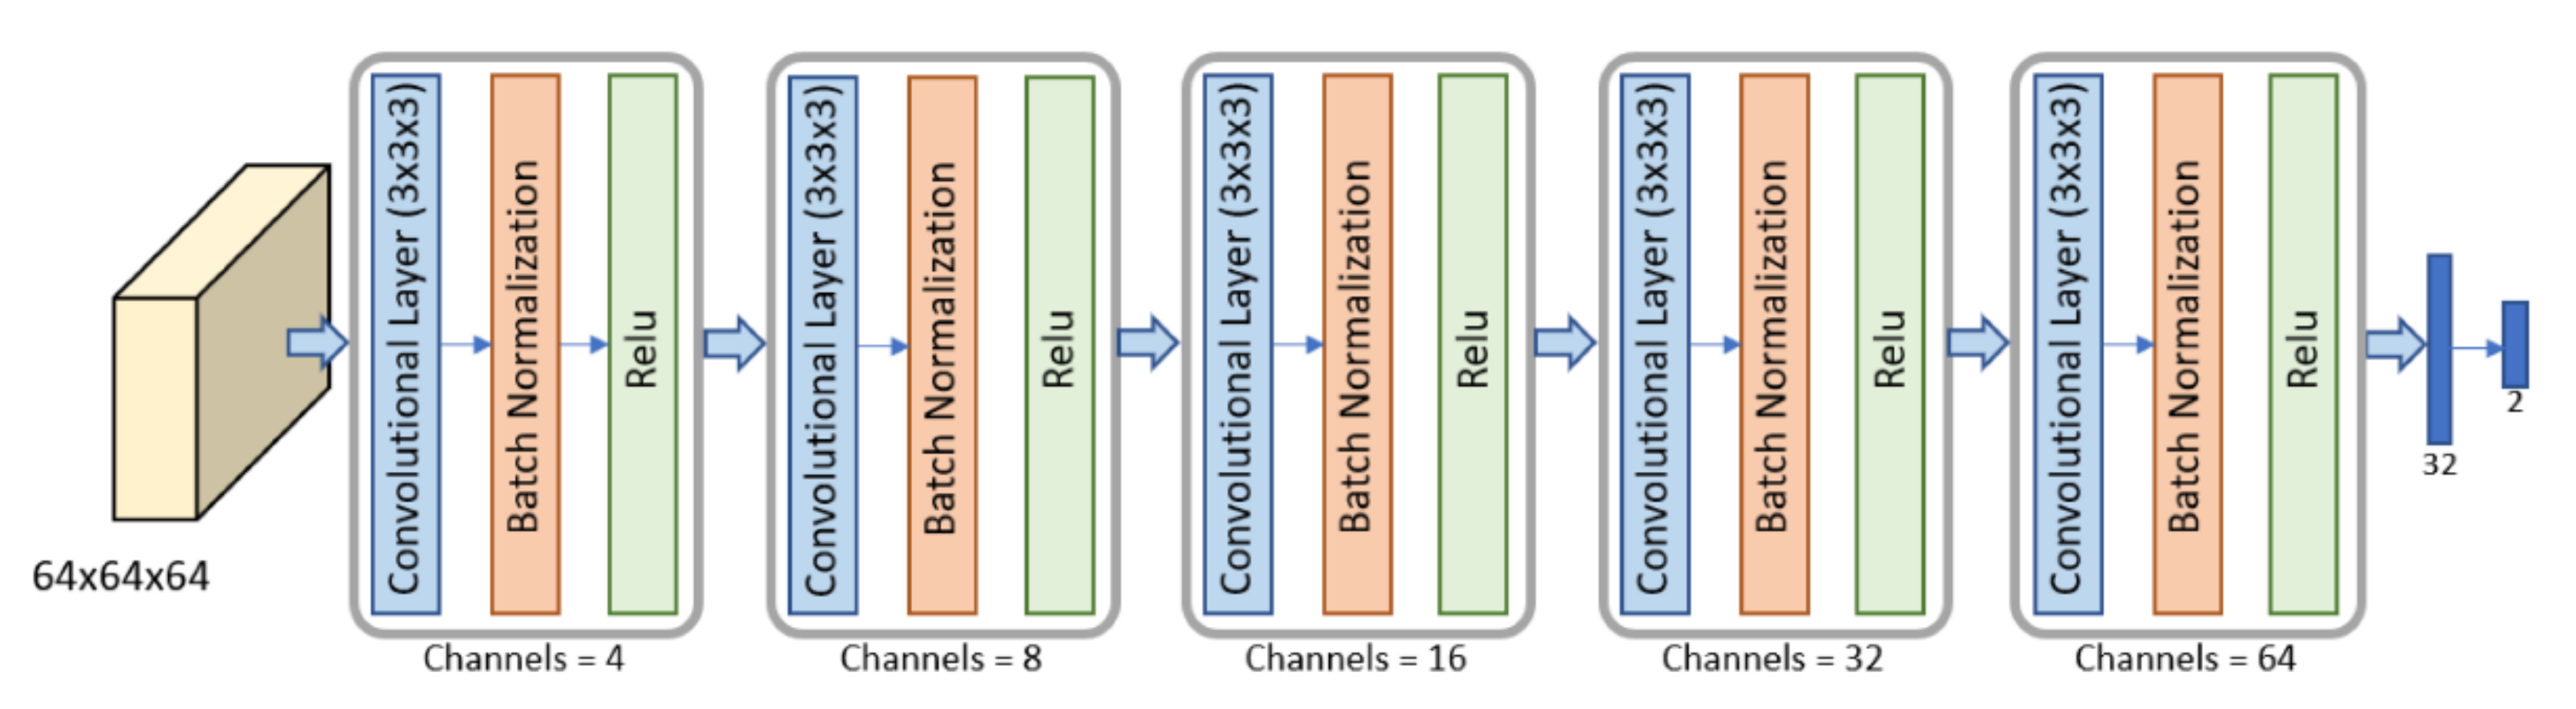

2.5. Volumes Extraction

2.6. Metastasis Prevision Assessment